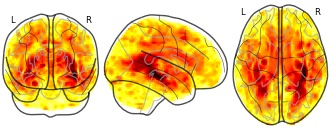

(2018). Longitudinal Analysis of Image Time Series with Diffeomorphic Deformations: A Computational Framework Based on Stationary Velocity Fields: t-map for the volume changes differences between the patients with Alzheimer's disease and the healthy control group (LLDF) [Dataset]. http://identifiers.org/neurovault.image:16314

glassbrain

Collection description

Subject species

homo sapiens

Modality

Structural MRI

Cognitive paradigm (task)

None / Other

Map type

T